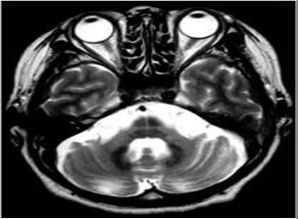

多系统变性主要影响我们的运动系统、自主神经系统和神经系统。简单来说,就是让我们动不了、感觉不到、控制不了。是不是听起来有点可怕?别担心,接下来我会详细给你介绍。

3. 神经系统:多系统变性还会影响我们的感觉和认知功能,让我们变得反应迟钝、记忆力下降,甚至出现痴呆症状。